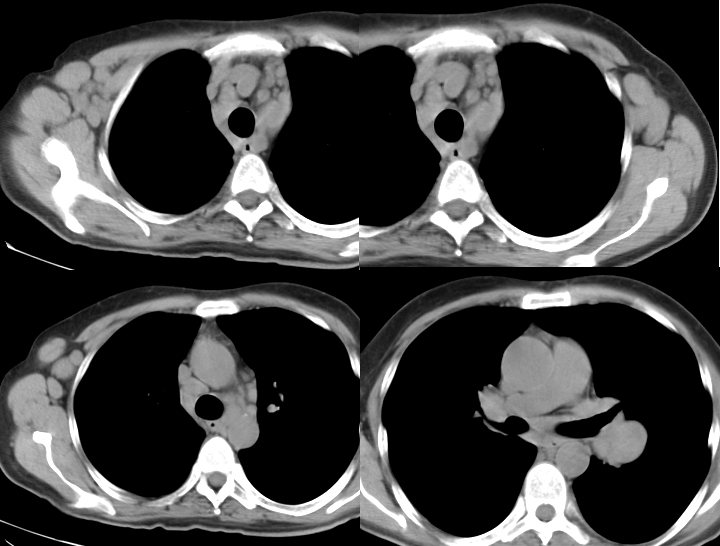

Gallery Mediastinum Lymphoma 9d

9d